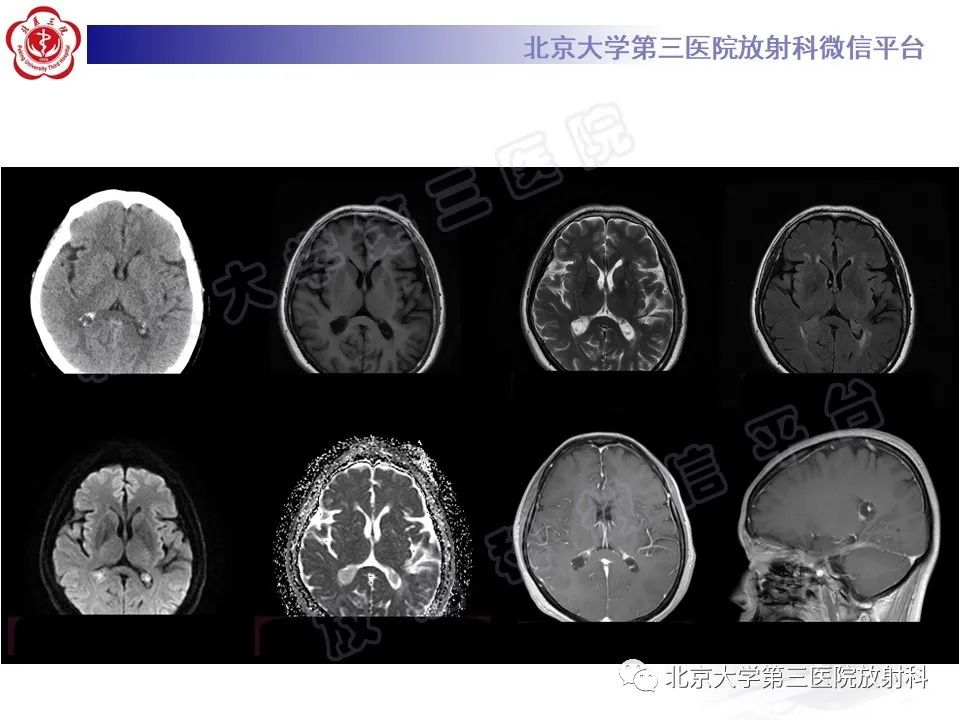

脉络丛黄色肉芽肿

【PPT】脉络丛黄色肉芽肿-1